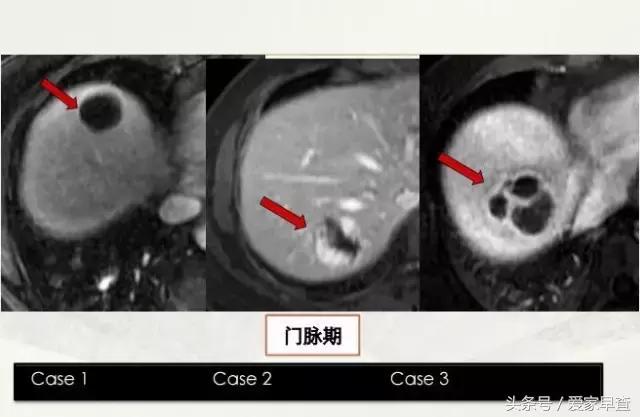

举个简单例子,比如说啊看这片子上一共有三个箭头,所指的都是三个很白的,我们管它叫高信号的囊性病变,但是你只靠这张片子你没办法诊断的它到底是什么。这三张片子是三个不同的病人三个不同的病。那我们下面看看他打了药之后,也就是做增强扫描之后的表现。

打了药之后,我们就能看到最左边这个是一个囊肿,而中间这个是血管瘤,右边这个是一个脓肿。这个简单的例子只是告诉大家对于肝脏的病变常规的检查是做增强扫描,也就是要做打药的。

尤其是当你第一次诊断的时候,也就是你想定性它到底是什么东西的时候,一定要做增强。当然,对于囊肿或血管瘤这两个比较常见的良性病变来说,当你第一次用增强扫描定了性之后,假如你只是随访观察它的大小的变化可以只做平扫,针对核磁而言。